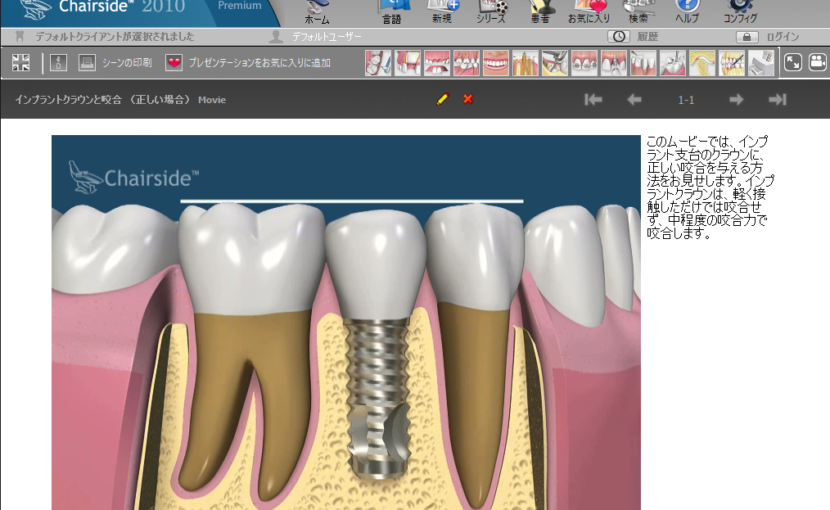

また、患者様のインプラント治療を予定している部分の骨も、同じ患者様であっても、骨の薄い部分、弱い部分、柔らかい部分などがあり、インプラントが最も安定しやすい部分を調べてから、手術時の最大の安定と、術後の長期的な安定の両方のバランスが取れた部分に、インプラントの長さや、太さ、角度などを決定し、インプラントの手術を行います。

また、この評価を経年的に評価し、レントゲンだけはわからない、骨密度の変化や、影響による、インプラントの調整を行うことで、たとえば、10年で骨の密度が20パーセント程度落ちた場合、インプラントの歯にかかる咬み合わせの力の負担も20パーセント程度調整するといった、インプラントのメンテナンスに応用しています。